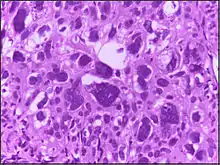

The phrase giant cell is also frequently used, especially with carcinoma.

Giant cell tumors include giant-cell tumor of bone, giant-cell tumor of the tendon sheath,[1] and giant cell fibroblastoma.[2]